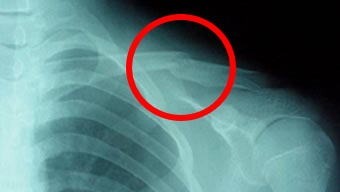

交通事故で鎖骨骨折いたしました!!

中井正之さまは、交通事故にて左鎖骨骨折を受傷されました。

クラビクルバンドにて鎖骨を約1か月固定しました。

その間、ふじた医院の交通事故治療で培ってきた治療法を活かした、電気治療(物理療法)、リハビリ、鍼灸を受けていただいています。

約1年経ち、痛みはなくなりましたが、手術もしていませんので、どうしても肩の可動域制限、鎖骨の変形の残存があります。

肩の痛み、可動域制限、鎖骨の変形が残る場合は、後遺障害に認定される可能性があります。

リハビリ、電気治療を続けることで、肩の痛み、手のしびれ、可動域制限が軽減され、今後さらに症状の改善が見込まれます。